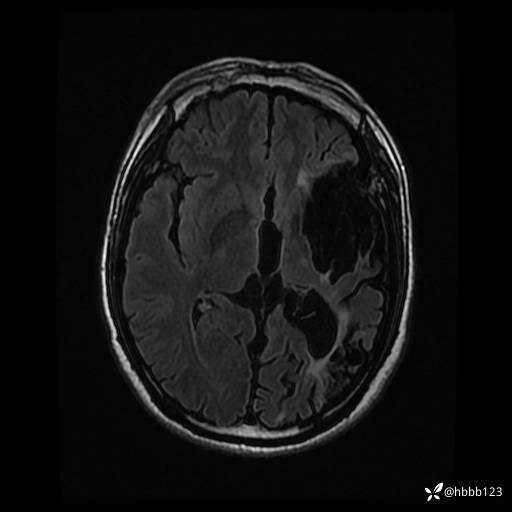

患者男,43岁。

简要病史:癫痫患者复诊,昨日发作5-6次,建议住院进一步治疗。

入院完善脑癫痫组合序列:

T2 Flair: